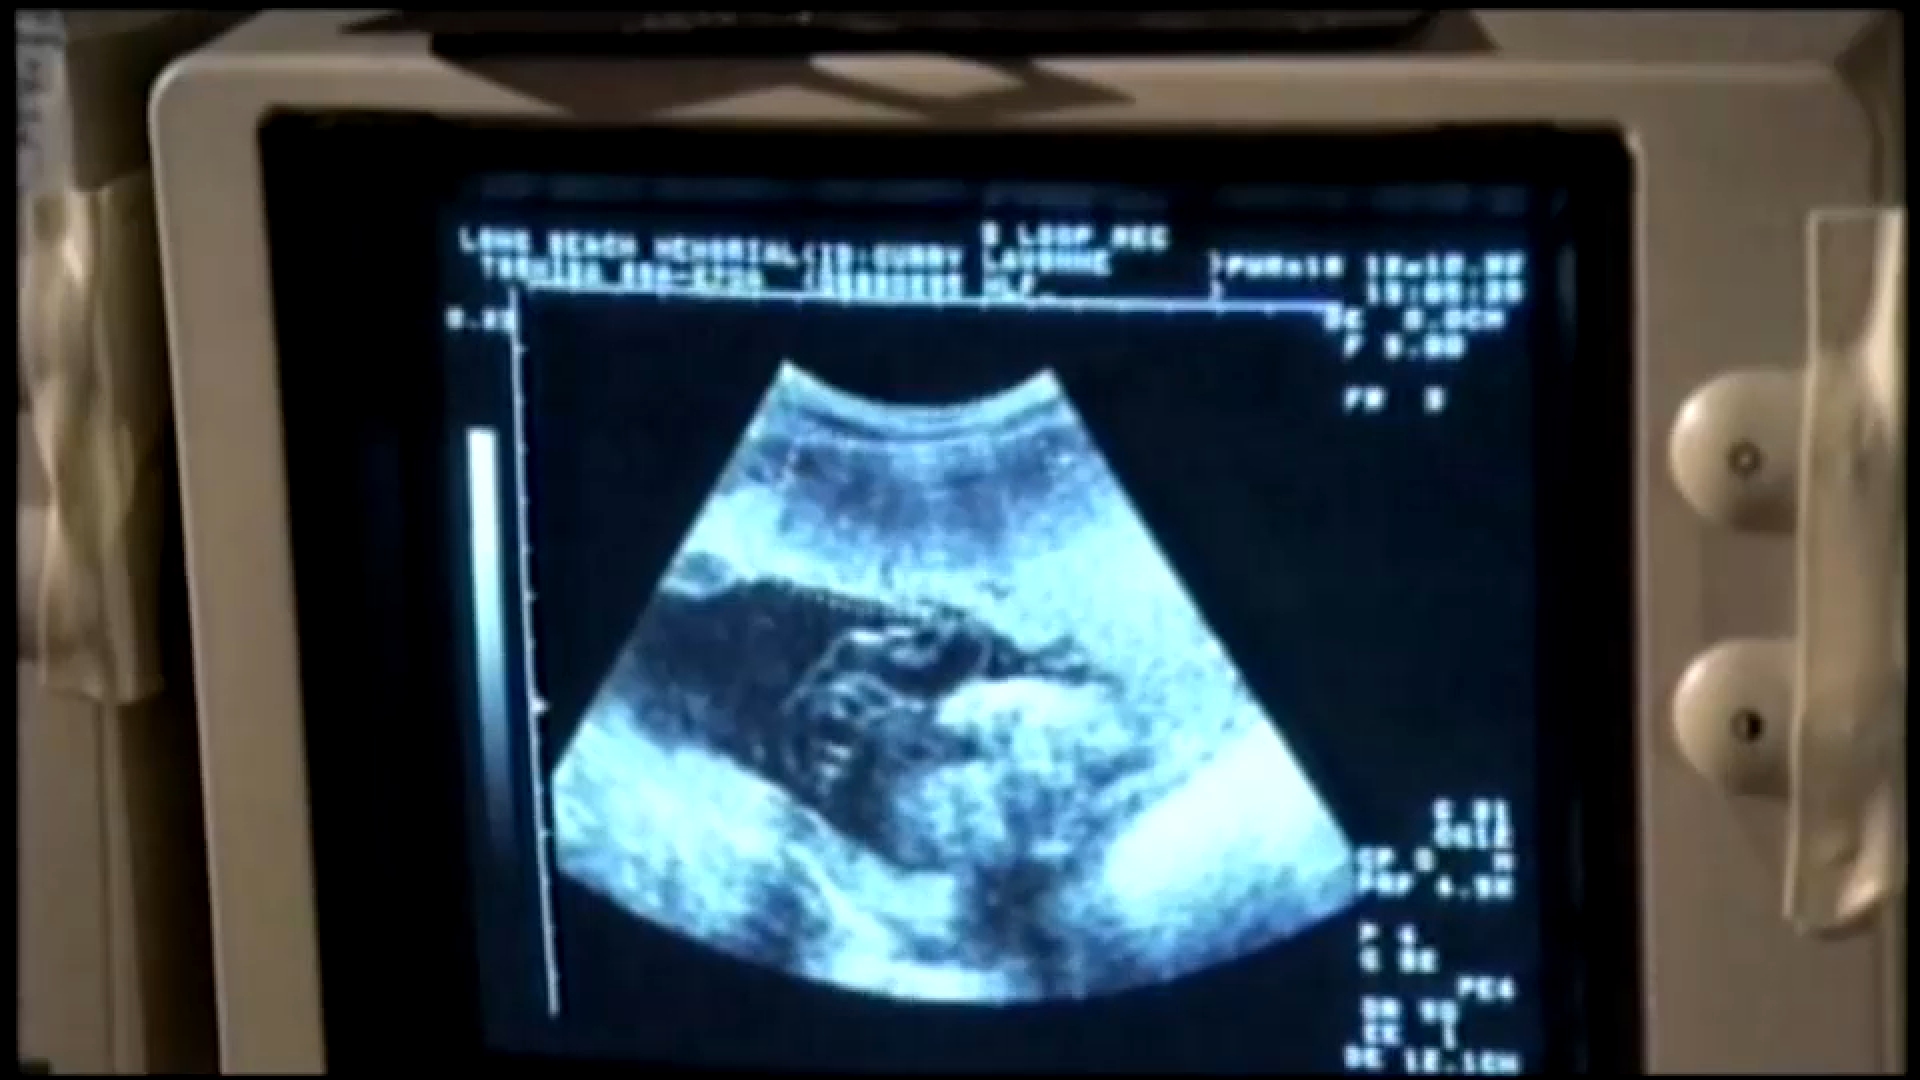

Using patient ultrasounds, a dedicated data team customizes digital twins—virtual representations of the uterus—enabling better understanding of the factors contributing to preterm birth. This approach aims to prevent the tragic outcomes that can accompany premature delivery.